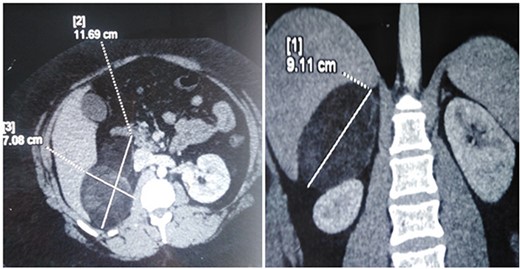

A 26-year-old female patient, presented with right flank pain evolving for 4 months. The clinical examination showed a morbid obesity with a body mass index of 42.8, a pulse at 85 bpm and normal blood pressure of 125/85 mmHg. CT showed a right retroperitoneal mass measuring 11 × 7 cm on the axial plane with a large axis of 9 cm. The mass appeared largely fatty with areas of higher attenuation inside. Density on CT varied between −90 Hounsfield units (HU) peripherally and −30 HU in the center (Fig. 1). Laboratory investigations were normal. A screening hormone test related to the adrenal gland revealed normal plasma catecholamine levels; epinephrine, 0.07 ng/ml (N: 0.00–0.10); norepinephrine, 0.28 ng/ml (N: 0.10–0.50). Furthermore, detailed 24-h urinalyses during hospitalization showed normal urinary catecholamine levels. The rest of the endocrine exploration was normal. The patient was taken up for exploratory laparotomy. Intraoperatively, a giant solid mass was found arising from the right adrenal gland and was adherent the upper pole of the kidney, duodenum and liver. The patient underwent excision of this adrenal mass. Macroscopically, the mass measured 12 × 8 × 10 cm and was round, well circumscribed and encapsulated. Histologically, the tumor was confirmed as a myelolipoma, and no malignant foci were detected (Fig. 2). The patient had an uneventful recovery and was discharged on the fifth post-operative day. Six months following the surgery the patient had no significant complaints and reported that her right flank pain had since subsided.